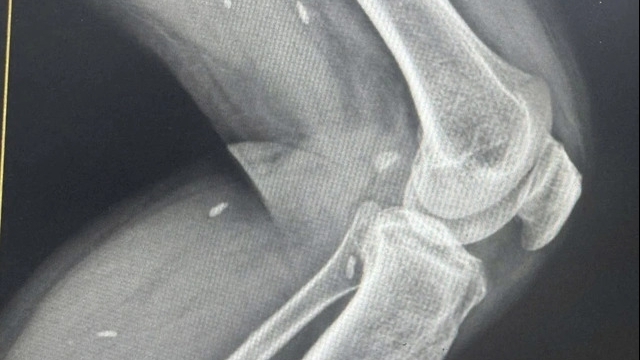

![]() |

| Các bác sỹ của Bệnh viện Đa khoa Mê Linh khám tổng quát cho người dân. |